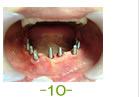

57歳 女性

治療後

インプラント21本 すべてジルコニア冠